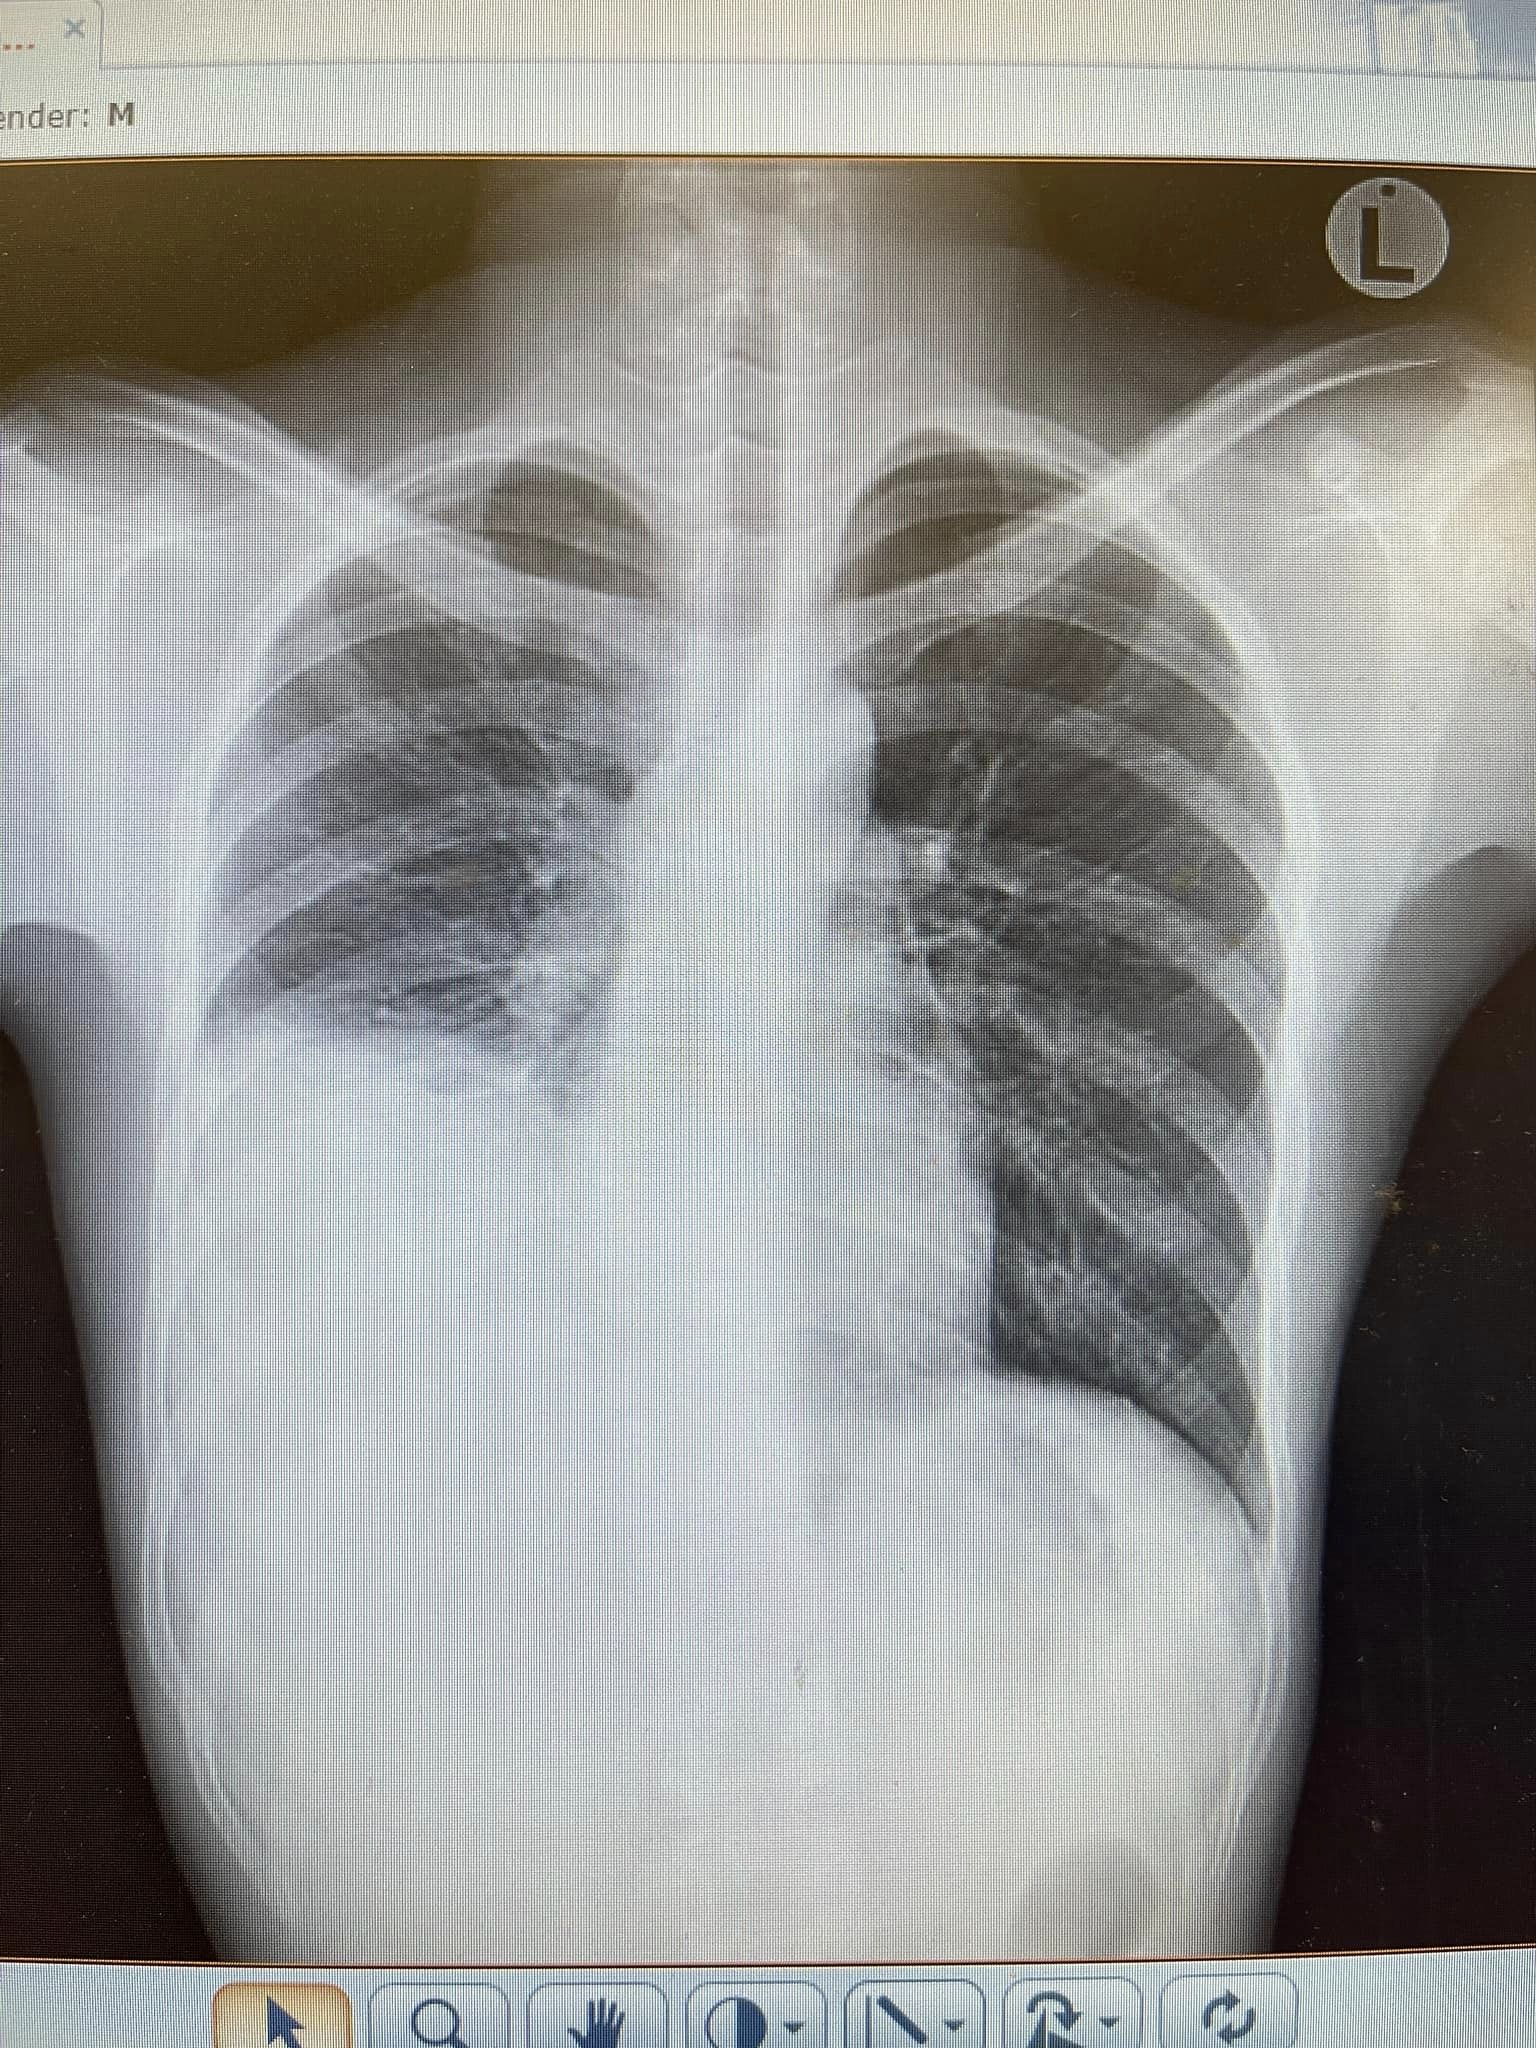

แกลเลอรีรูปภาพ หมอเตือน ตั้งสติก่อนกินตำปูปลาร้า คนไข้อายุ 15 เอกซเรย์ปอดเจอ "โพรงฝีหนอง" 10 ซม.

8 ภาพ หมอเตือน ตั้งสติก่อนกินตำปูปลาร้า คนไข้อายุ 15 เอกซเรย์ปอดเจอ "โพรงฝีหนอง" 10 ซม.

รูปภาพของ หมอเตือน ตั้งสติก่อนกินตำปูปลาร้า คนไข้อายุ 15 เอกซเรย์ปอดเจอ "โพรงฝีหนอง" 10 ซม.

อัลบั้มภาพทั้งหมด หมอเตือน ตั้งสติก่อนกินตำปูปลาร้า คนไข้อายุ 15 เอกซเรย์ปอดเจอ "โพรงฝีหนอง" 10 ซม.